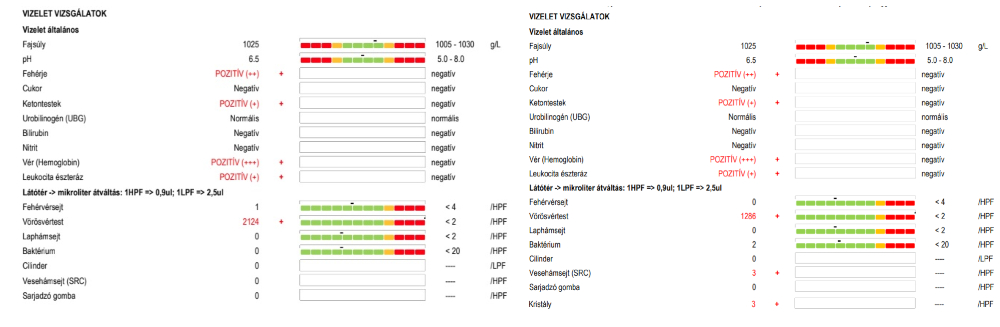

Február 8-án leadtuk a véres a vizeletet, melynek eredményét úgy kellett telefonon kikérni, szinte alig adták ki, mert olyan brutális, ezerszeres vérvizelés értékeket (2124 illetve 1286 vörösvértest/látótér) jelzett a vizsgálat, amilyennel szinte nem találkoztak, magánbeteg által leadott mintáknál szinte biztosan nem – mert aki ilyen beteg egyből állami kórházi ellátást kap civilizált országokban. A normális tartomány határa 2 vörösvértest látóterenként, a vizsgálat pedig vér+++, proteinuria ++, ketonuria +, leukocyta észteráz + értékeket mutatott. A Synlab az egyetlen megbízható pont volt számunkra, amely rengeteg vizeletvizsgálatot és egyéb labormunkákat végzett nekünk, rengeteg pénzt kellett otthagynunk.